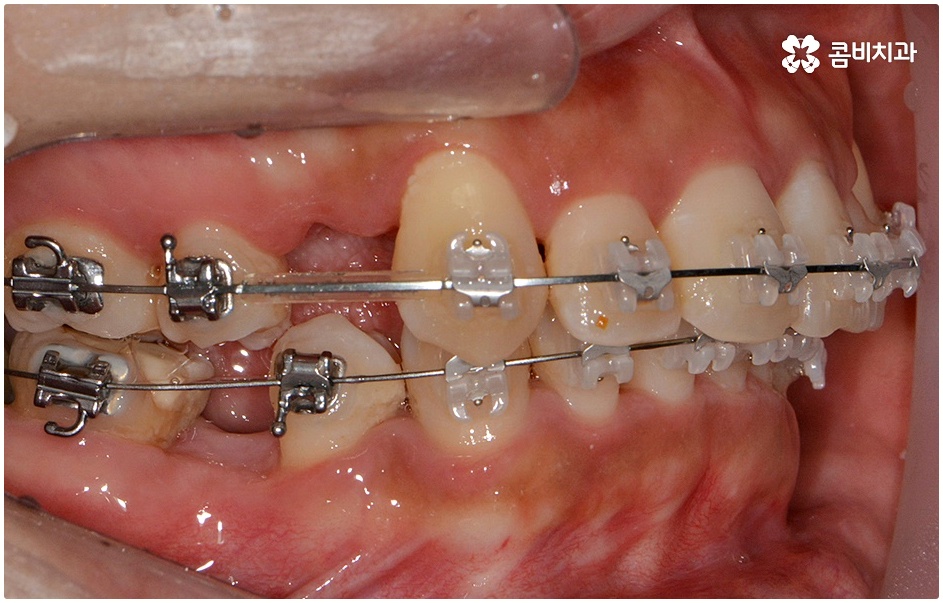

치료를 위해서는 입을 안쪽으로 넣기 위한 공간을 확보해야 하므로 보통 위아래 소구치 총 4개의 치아를 발치하여 그 공간을 활용해 튀어나온 치아와 잇몸을 전체적으로 뒤로 이동시키는 방법을 사용하나 최근에는 미니스크류, 치간 삭제 등의 방법을 이용하여 비발치 교정을 진행하기도 하니 먼저 자신의 상황을 꼼꼼하게 살펴보고 부정 교합의 원인과 정도부터 정확하게 파악하는 것이 필요한 거에요.